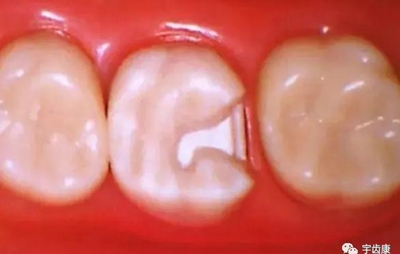

箱型固位形

溝固位形

釘洞固位形